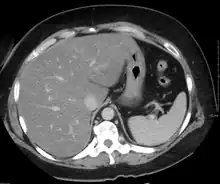

Medical imaging

On X-ray computed tomography (CT), the increased fat component will decrease the density of the liver tissue, making the image less bright. Typically the density of the spleen and liver are roughly equivalent. In steatosis, there is a difference between the density and brightness of the two organs, with the liver appearing darker.[12] On ultrasound, fat is more echogenic (capable of reflecting sound waves). The combination of liver steatosis being dark on CT and bright on ultrasound is sometimes known as the flip flop sign.

On magnetic resonance imaging, multiecho gradient echo images can be used to determine the percent fat fraction of the liver.[13] The different resonance frequencies between water and fat make this technique very sensitive and accurate. Acquisition of echoes in "in phase" and "out phase" conditions (pertaining to the relative phases of the fat and water proton contingents) enables to obtain a signal proportional to the water and fat contingent, or a signal proportional to the water minus the fat contingent. These signal intensities are then algebraically combined into a percent fat. More recent techniques take into account experimental noise, signal decay and spectroscopic properties of fat. Numerous validation studies have demonstrated excellent correlations between the steatosis level quantified at MRI and the steatosis levels semi-quantitatively and quantitatively determined on liver biopsies (reference methods). Several MRI vendors offer automated calculation of percent fat with acquisition sequences no longer than a single breath hold.

On abdominal ultrasonography, steatosis is seen as a hyperechoic liver as compared to the normal kidney.